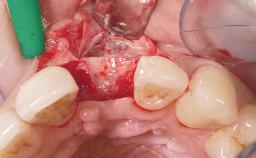

Late Placement of an Implant in a Maxillary Left Central Incisor Site

A 36-year-old female patient was referred for the replacement of the upper left central incisor (tooth 21), which had fractured. Although the tooth had been asymptomatic for many years, the crown began to loosen, at which time she presented to her dentist for an assessment. Teeth 21 and 22 had both been endodontically treated many years previously. She was a healthy individual and a non-smoker.

Bone Augmentation Horizontal|Staged

Augmentation Materials Xenogenous|Membrane

Bone Volume Deficient horizontally, requiring prior grafting